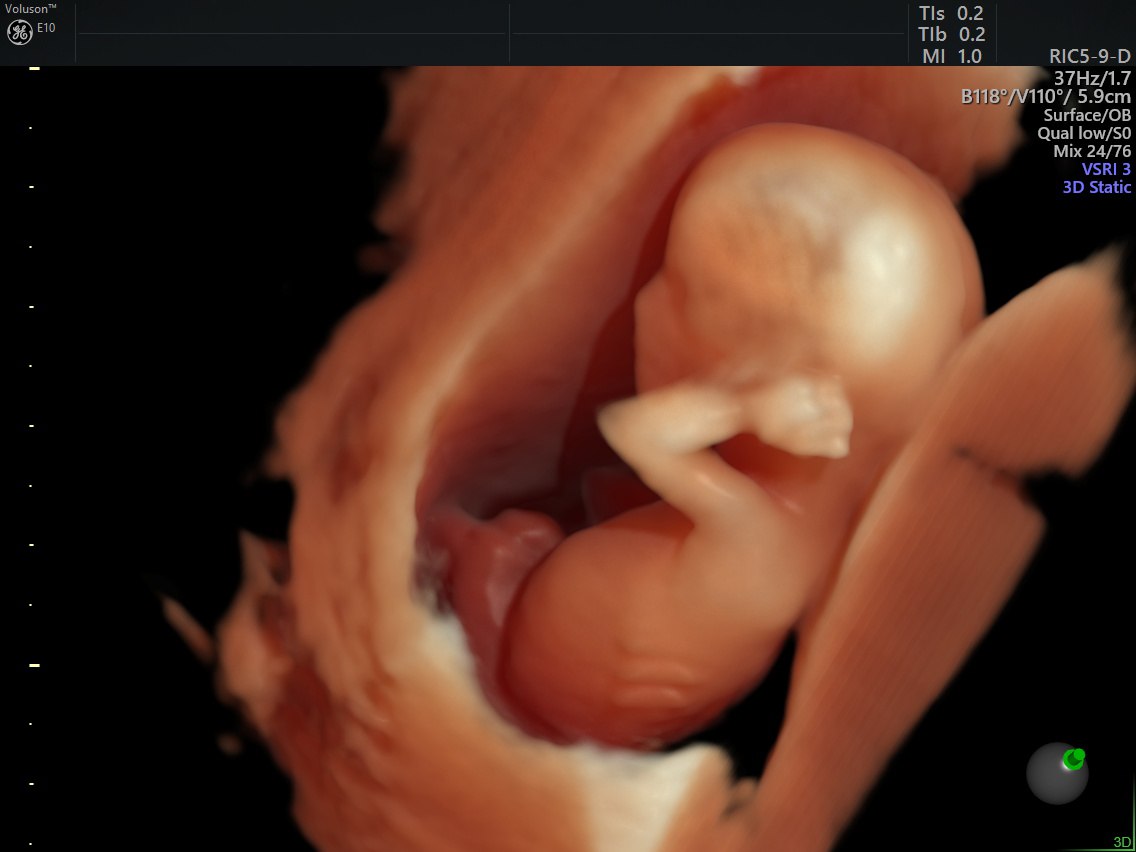

• Экспертное УЗИ I, II, и III триместров

• Биохимический и ультразвуковой скрининги

• Аппарат Voluson E10 — для проведения ультразвуковых исследований.